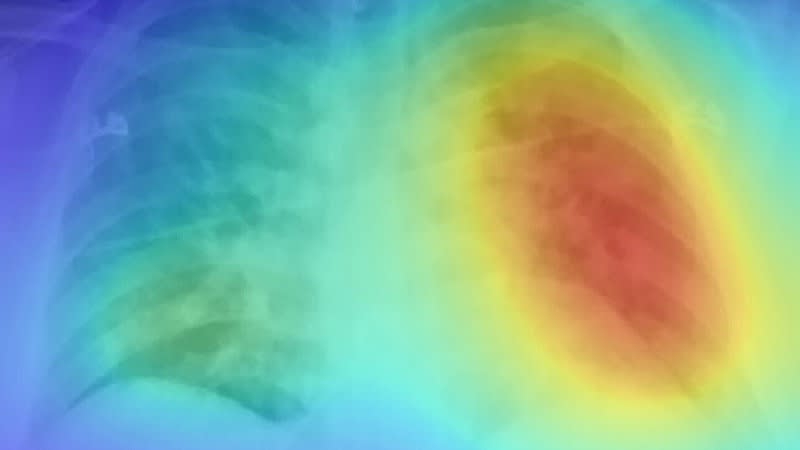

A new artificial intelligence platform detects COVID-19 by analyzing x-ray images of the lungs. Called DeepCOVID-XR, the machine-learning algorithm outperformed a team of specialized thoracic radiologists — spotting COVID-19 in x-rays about 10 times faster and 1–6 percent more accurately.

To develop, train, and test the new algorithm, the researchers used 17,002 chest x-ray images — the largest published clinical dataset of chest x-rays from the COVID-19 era used to train an AI system. Of those images, 5,445 came from COVID-19-positive patients from sites across the Northwestern Memorial Healthcare System.

The team then tested DeepCOVID-XR against five experienced cardiothoracic fellowship-trained radiologists on 300 random test images from Lake Forest Hospital. Each radiologist took approximately two-and-a-half to three-and-a-half hours to examine this set of images, whereas the AI system took about 18 minutes.